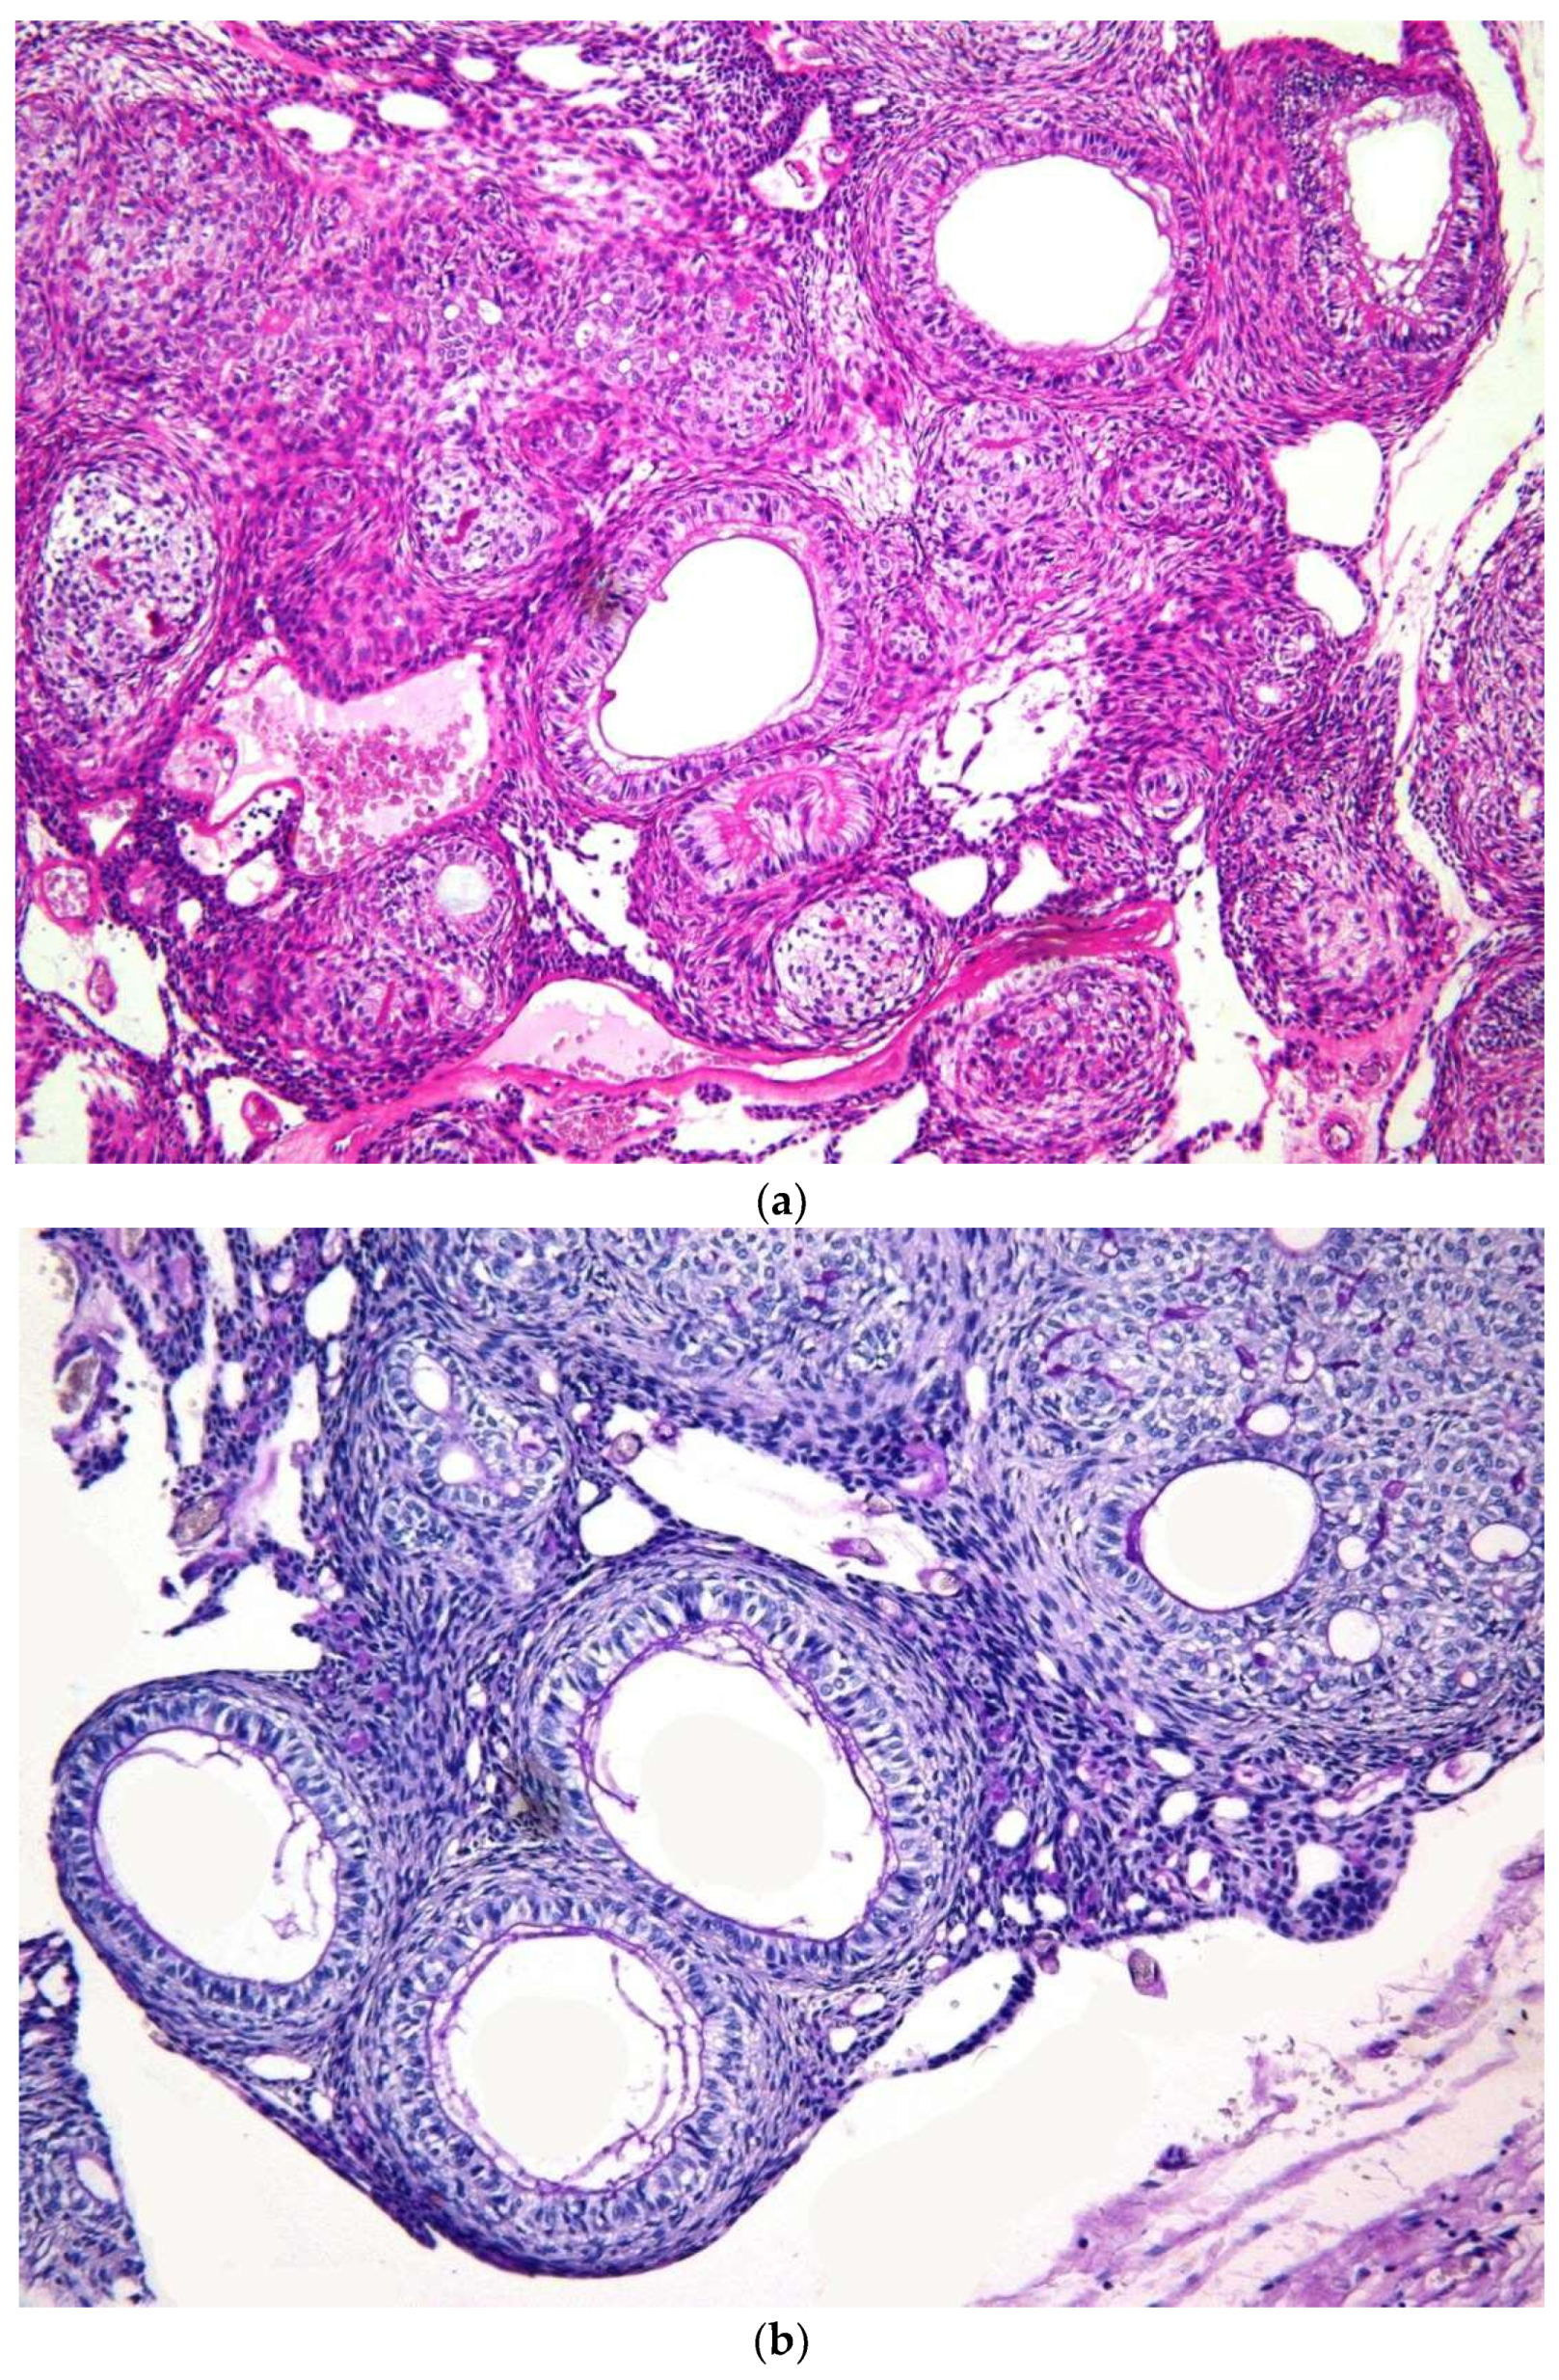

| Histopathology | ||||

| 1. Capsule-present | 10 (90.9) | 24 (80.0) | 34 | |

| 2. Epithelial component | ||||

| 2a. Duct like structures | 09 (81.8) | 27 (90.0) | 36 | |

| 2b. Epithelial whorls | 11 (100) | 29 (96.6) | 40 | p = 0.7 |

| 2c. Rosettes | 03 (27.2) | 19 (63.3) | 22 | |

| 2d. Trabeculae | 08 (72.8) | 25 (83.3) | 33 | |

| 3. Stromal component | ||||

| 3a. Tumour droplets | 08 (72.8) | 20 (66.6) | 28 | |

| 3b. Calcifications | 11 (100) | 29 (96.6) | 40 | p = 0.8 |

| 3c. Osteo-dentine | 01 (09.1) | 01 (03.3) | 02 | |